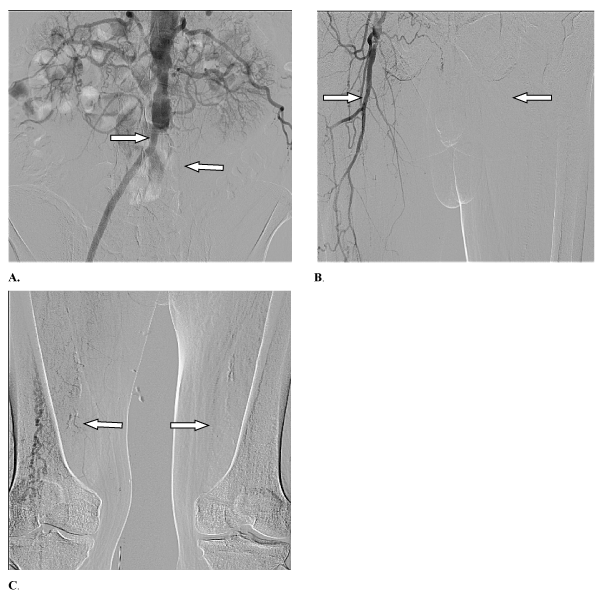

After his discharge from the hospital, this patient had noticed that the pain increased again in the left lower extremity. Also the cyanosis of the skin of the left foot has appeared. The patient was admitted again to the local vascular center and digital subtraction angiography (DSA) was performed to assess progression of his disease. The findings of this imaging procedure indicated multiple sites of thrombosis (Figure 2A-2C).

Figure 2. Findings of digital subtraction angiography (DSA) which was performed to assess progression of the disease. A. The right branch of the aortobifemoral bypass was detected on the angiogram of the abdominal aorta and pelvis’s arteries before the last surgical procedure, however the left one was found to be thrombosed by DSA. B. The right anastomosis of the aortobifemoral bypass is shown on the angiogram of the thighs, however arteries of the left thigh, including the left profunda femoral artery were not detectable. C. The arteries of the left lower extremity were not detectable on the angiogram of the thighs and popliteal areas